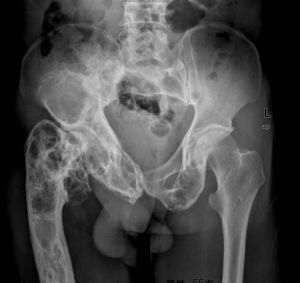

一、病灶多發生於四肢長骨,尤以股骨和脛骨為多見,其次為肋骨、顱面骨、骨盆和手、足小骨,而脊柱較為少見。

二、X線上,病灶的密度常有差異,取決於病理成分,病灶如主要為纖維組織常表現為囊狀透光區;如主要為砂礫樣鈣化新生骨者常呈磨砂玻璃狀;如新生骨鈣化較多時則表現為一片明顯的增白區。每一病灶,可以上述表現按不同比例組合出現。

3、位於長、短管狀骨和肋骨的病灶多發生於骨幹或骨骺端,病骨膨脹而變粗大,常呈單房透明或磨砂玻璃狀,範圍較大,其中可有緻密骨嵴沿骨長軸方向走行向內凸出,使病灶呈不完全的分房狀如“絲瓜囊”。有時在病灶內可見或大或小的片狀鈣化影。

骨纖維異常增殖症①變形性骨炎型:常為多骨型病變表現,其特點是顱骨增厚,顱骨外板和頂骨呈單側泡狀膨大,骨內板向板障和顱腔膨入,增厚的顱骨中常見局限和瀰漫的射線透明區和濃密區並存,這種骨吸收與硬化並存極似Paget變形性骨炎的表現。顱骨擴大和硬化,可從額骨擴大到枕骨。面部受累可導致眶和鼻腔狹窄及鼻竇腔消失,此型約占56%。②硬化型:此型多見上頜肥厚,可致牙齒排列不整,鼻腔、鼻竇受壓變小。上頜骨受累多於下頜骨,且多為單骨型。損害呈硬化或毛玻璃樣外觀。相反,下頜骨損害多見於多骨型,表現為孤立的骨壁光滑且可透過射線。此型約占23%。③囊型:顱骨呈孤立或多發的環形或玫瑰花形缺損,缺損從菲薄的硬化緣開始,其直徑可達數厘米。孤立的損害有似嗜酸性肉芽腫,多發的缺損可誤認為HandSchüllerChristian病,偶有數種X線類型出現於同一個體上。此型約占21%。套用CT或MRI檢查,能明確病變的位置和範圍,且能顯示與軟組織的聯繫。定期檢查可動態觀察病變的發展程度,對選擇術式進路、減少併發症和估計預後甚為重要。